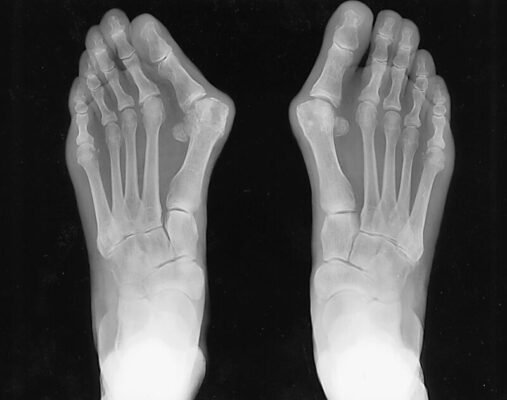

Hình ảnh học

Phim chụp X quang đơn giản chịu trọng lượng sẽ cung cấp hầu hết các thông tin cần thiết. Hình chụp trước sau (Hình 3) thể hiện góc (Hình 4) giữa xương bàn chân thứ nhất và thứ hai (góc giữa các xương bàn chân). Cũng cần đánh giá dấu hiệu thoái hóa khớp bàn ngón thứ nhất.